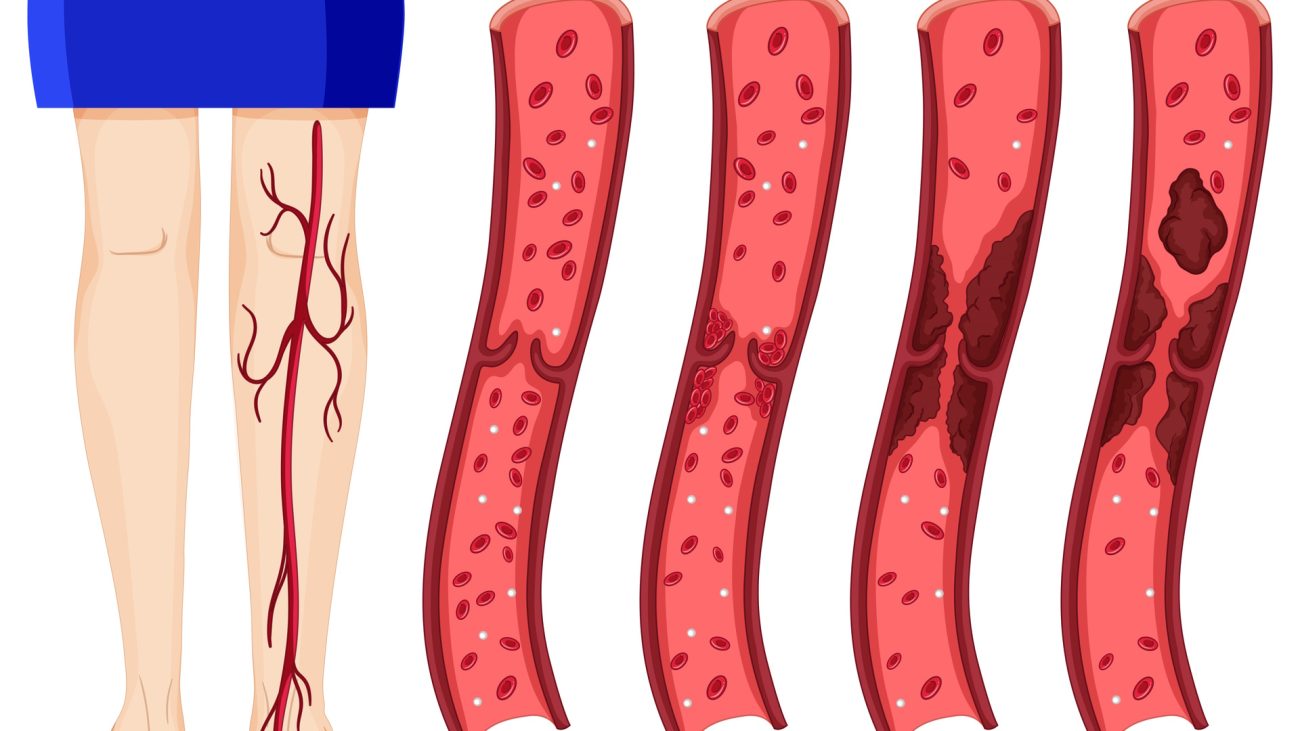

انسداد عروق عمقی پا

انسداد عروق عمقی پا (ترومبوز ورید عمقی): علل، علائم و درمان انسداد عروق عمقی پا که با نام ترومبوز ورید عمقی (DVT – Deep Vein Thrombosis) شناخته میشود، یک بیماری جدی است که در آن لختههای خونی در وریدهای عمیق پا ایجاد میشوند. این وضعیت میتواند خطرناک باشد، زیرا ممکن است لخته به ریهها حرکت […]